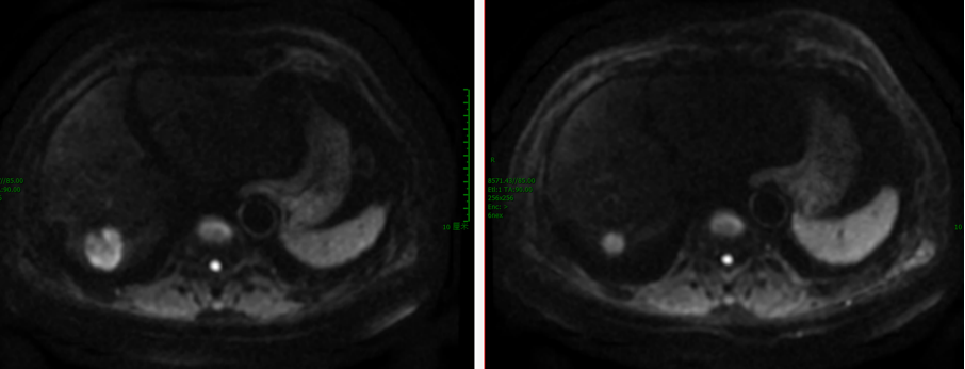

【贝伐珠单抗+雷替曲塞+奥沙利铂】2020-2-11 上腹部MRI增强:“直肠CA根治术+肝转移瘤切除术+胆囊切除术”后改变,与前片(2019-5-9)相仿,肝右叶局部强化欠均,但未见明确的占位性病变。

2020-3-6 胸部CT:两肺多发小斑点灶及微小结节,直径约3-10mm,较前(2019-11-05)部分增大。评估病情PD。

2020-4-17 至 2020-8-13 予三线第1-6疗程奥沙利铂、雷替曲塞联合贝伐珠单抗化疗。